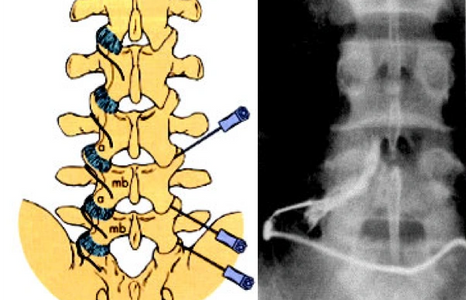

Diagnosis, from history, examination and imaging, helps advise on natural history, provide reassurance and outline potential treatment strategies for the whole range of spinal conditions. Scanning can help to rule out problems but standing X-rays in some patients are sometimes invaluable as we see the spine under load

Mr Harding undertakes all aspects of spinal surgery, from microsurgery through to complex reconstruction in adults and children for spinal deformity in all regions of the spine. Specific details can be found in 'Conditions' and 'Treatments'